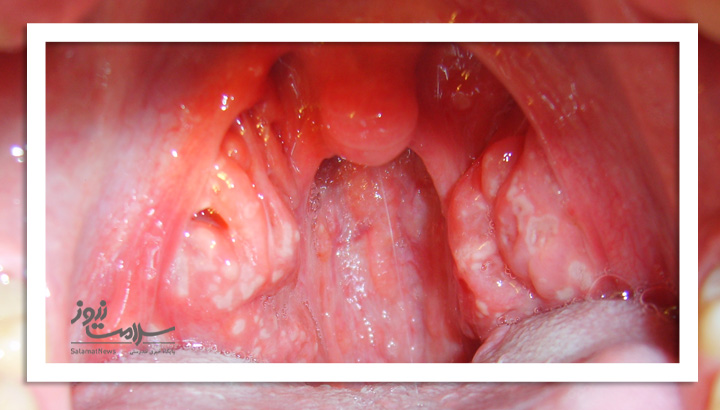

عکس لوزه سالم و ناسالم

- لکه های سفید رنگ روی لوزه ها - یا یک پوشش سفید، زرد یا خاکستری روی لوزه ها